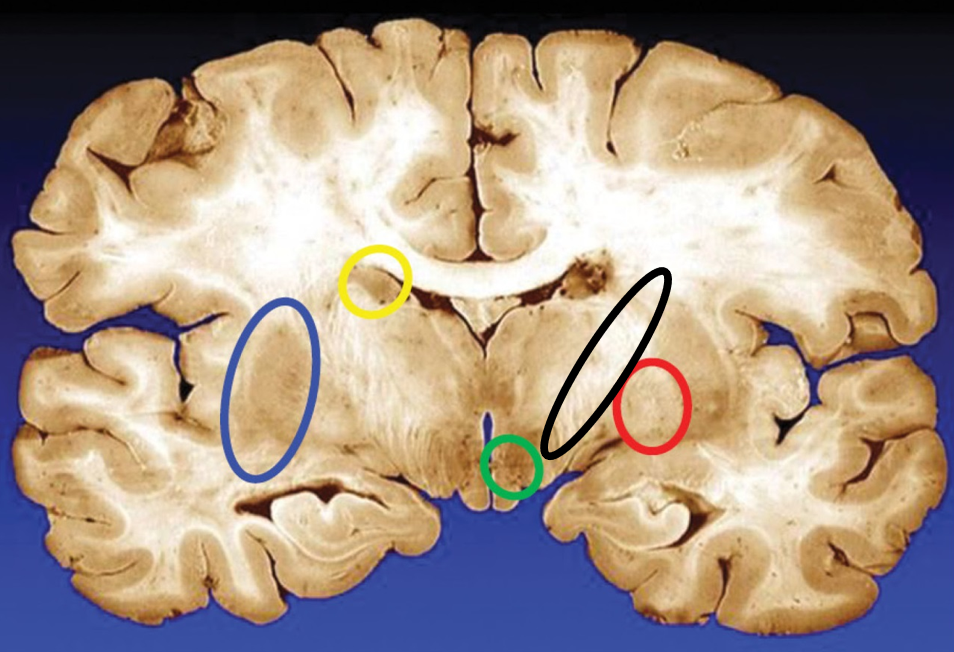

blue

putamen

yellow

caudate

green

subthalamic nuclei

black

internal capsule

red

globus pallidus